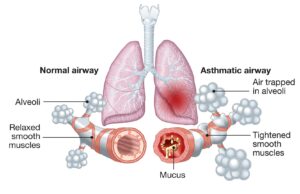

Astma